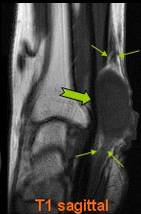

COMPRESIUNEA NERVULUI ULNAR PRIN OSTEOCONDROM SECUNDAR

Parestezii in teritoriul nervului ulnar Mica osificare →in contact cu n. Ulnar → Pe IRM mica lacuna osteocondrala a condilului →* corespunzator locului de plecare a osteocondromului